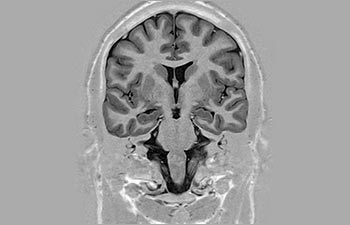

1 In base a uno studio interno in cui si confronta il flusso di lavoro con il sistema RM Achieva. 2 ComforTone sarà disponibile con Prodiva 1.5T a partire da fine 2017. 3 In base a uno studio interno che ha confrontato il flusso di lavoro di una serie di applicazioni su cervello, colonna vertebrale, apparato muscoloscheletrico e corpo con il sistema RM Achieva. 4 Per normale funzionamento si intende una scansione tipica eseguita in condizioni di disponibilità ininterrotta di elettricità, con raffreddamento del magnete e senza interventi di assistenza. 5 A seconda di quanto previsto nel contratto e della disponibilità locale. 6 "Altri" si riferisce a sistemi RM 1.5T da 60 cm per il corpo intero